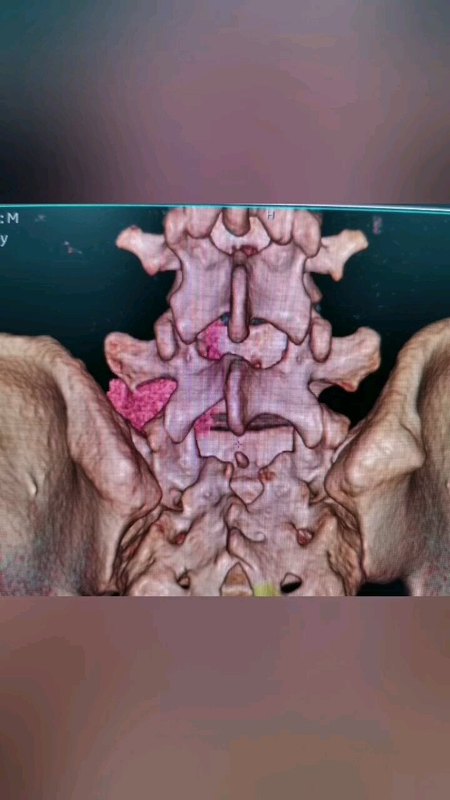

脊柱也長腫瘤嗎?